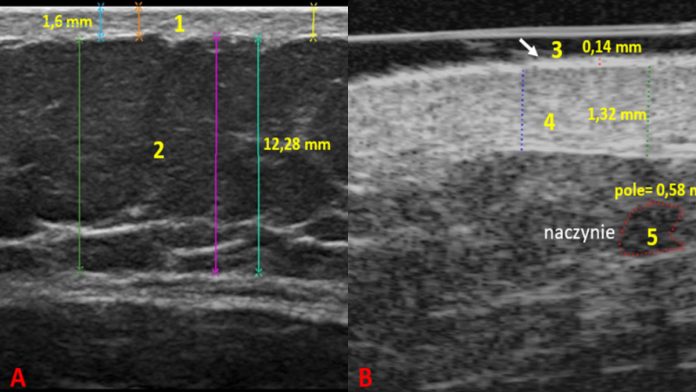

Ultrasonografia (USG, ultrasonography) od dziesięcioleci stanowi kluczową metodę diagnostyczną w medycynie. Powszechne wykorzystywanie ultrasonografii w takich dziedzinach, jak kardiologia, ginekologia czy chirurgia naczyniowa, potwierdza jej wysoką użyteczność jako metody nieinwazyjnej, bezpiecznej, rzetelnej i powtarzalnej. W ostatnich latach USG rozszerzyło swój zakres, obejmując nowe dziedziny i dostarczając szczegółowych wizualizacji struktur, które dotychczas były poza jego zasięgiem. Jednym z takich obszarów, w którym ultrasonografia zyskuje na znaczeniu, są badania największego narządu ciała człowieka, jakim jest skóra.